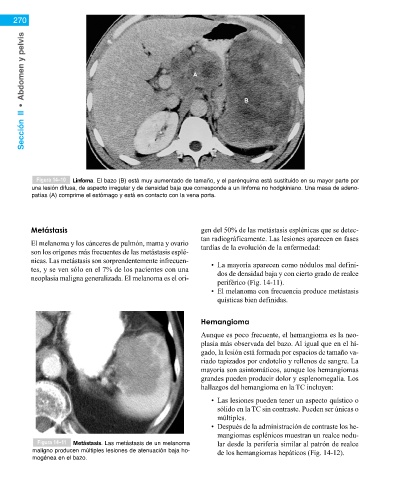

Figura 14–10 Linfoma. El bazo (B) está muy aumentado de tamaño, y el parénquima está sustituido en su mayor parte por

una lesión difusa, de aspecto irregular y de densidad baja que corresponde a un linfoma no hodgkiniano. Una masa de adeno-

patías (A) comprime el estómago y está en contacto con la vena porta.